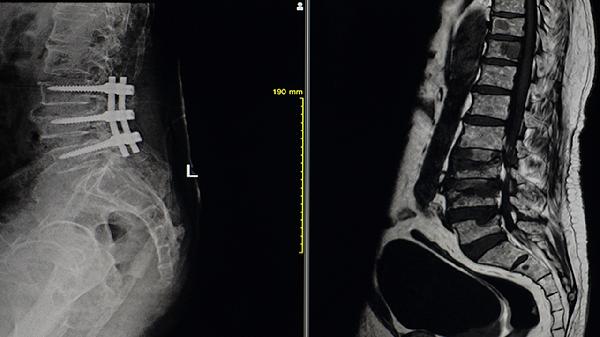

严重脊柱畸形患者可考虑脊柱矫形手术。髋关节严重受累时需行全髋关节置换术。手术风险较高,需由专业团队评估适应症。术后仍需配合药物和康复训练。